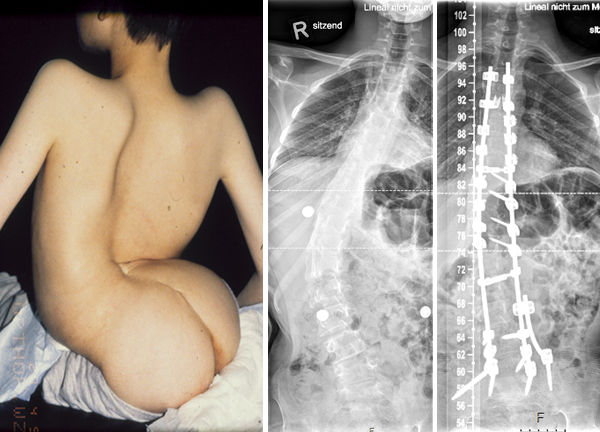

Auch Wirbelsäulenverkrümmungen (Skoliose) sind insbesondere bei den Schwerst-Betroffenen Patienten häufig. Sie führen im Verlauf zu Schmerzen, die Sitzfähigkeit und insbesondere auch die Atmungsaktivität werden beeinträchtigt. Als Folge leiden die Kinder oder Jugendlichen häufig an Infekten der Atemwege. Wie auch bei der Hüftluxation ist Prophylaxe am besten. Sollte sich dennoch eine ausgeprägte Verkrümmung entwickelt haben, profitieren die Jugendlichen und insbesondere auch die Pflegenden funktionell sehr von einer Operation, bei der die Wirbelsäulenverkrümmung weitestmöglich korrigiert wird und der Rücken stabilisiert wird.